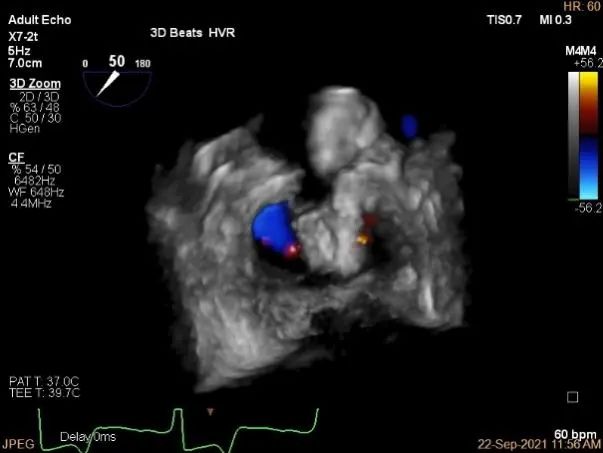

三维评估两个夹子位置

3D-color再次确定未见残余分流

评估瓣口条件,平均跨瓣压差:4mmHg